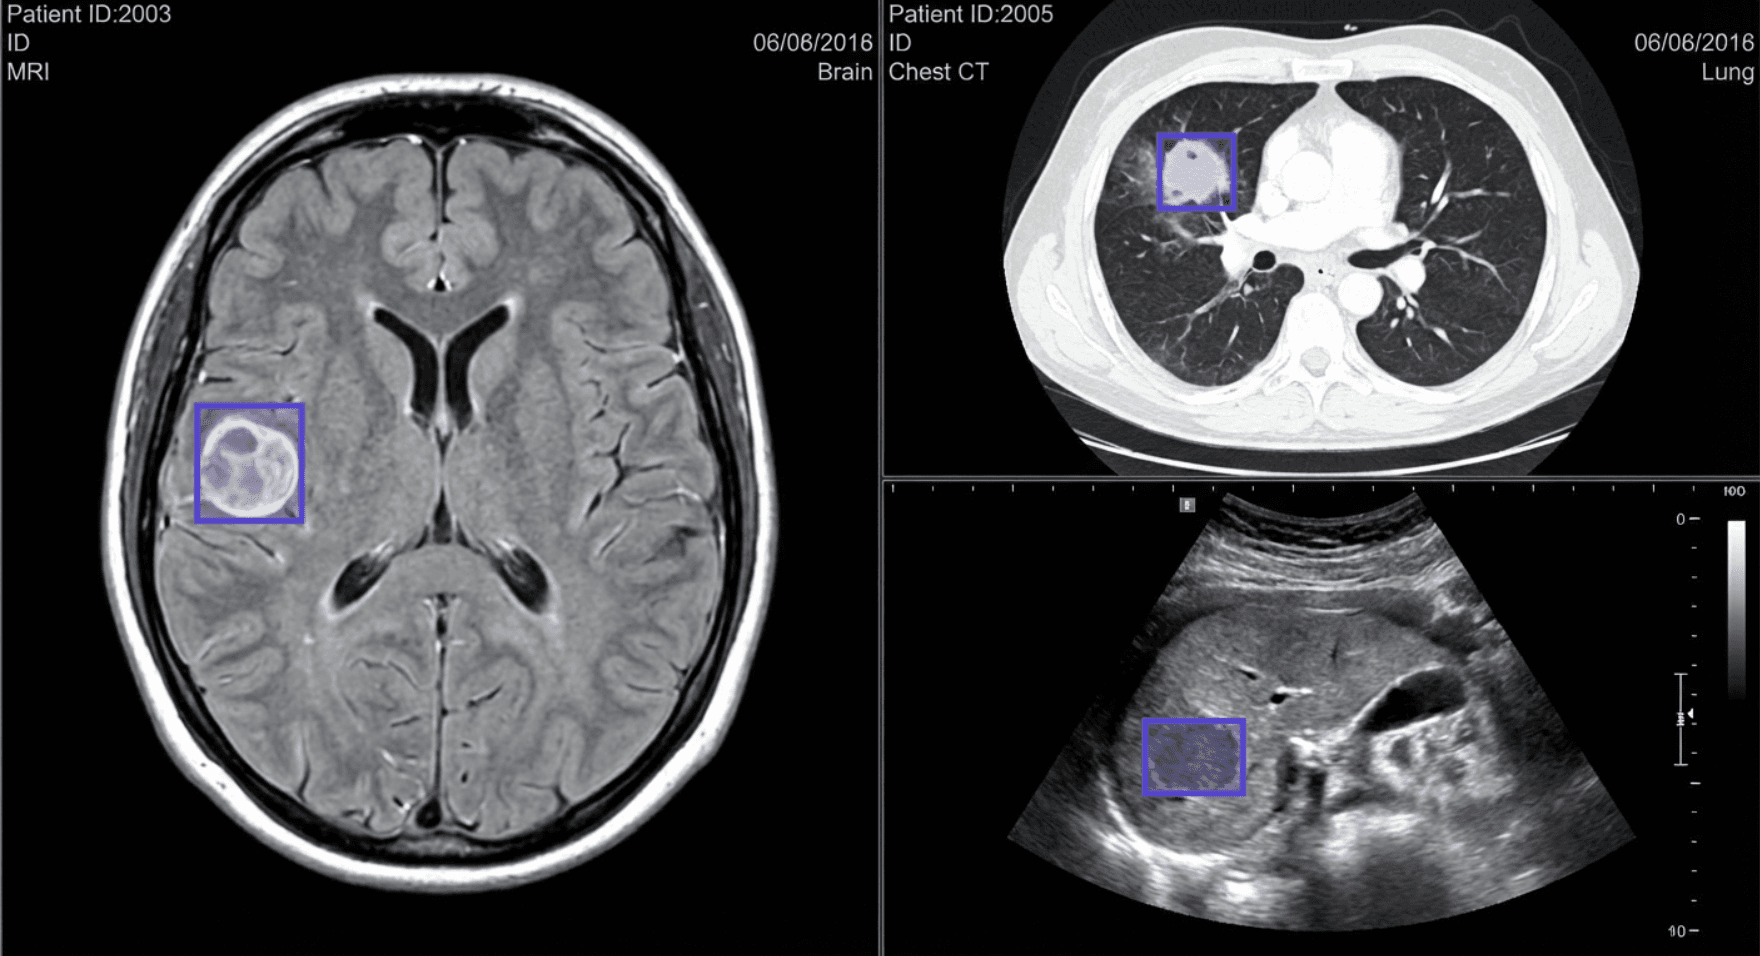

BionomeeX’s AI tools analyze MRI, CT, ultrasound, and radiology scans to:

Automatically identify organs, tissues, and anomalies

Enable monitoring of patient progression over time

By combining automated processing with Human-in-the-Loop validation, the platform ensures high accuracy, consistency, and drastically reduced analysis time.

As the AI learns iteratively from human feedback, its performance improves continuously, producing robust, clinically actionable insights.